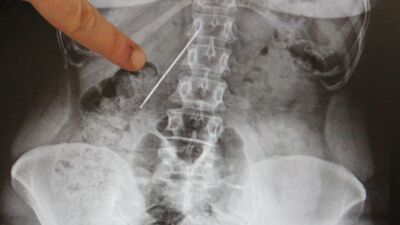

AA'nın haberine göre; doktorlar çekilen filmde hastanın karın bölgesinde 15 santimetre uzunluğunda bir iğne tespit etti. Bir hafta sonra ameliyata alınan Çalışkan'ın vücudundaki iğne yerinden kaydığı için çıkarılamadı. Başarısız geçen operasyonun ardından çekilen filmde, iğnenin hastanın sağ böbrek ile kalın ve ince bağırsağa yakın yerde olması nedeniyle yeni bir operasyon yapılamadı.

İğnenin zamanla hastanın yaşam kalitesini etkilediğini ifade eden Arazi, "Bu iğne çok tehlikeli bir yerdeydi. Sağ böbreğe yakın bir yerle, ince ve kalın bağırsak arasında duruyordu. Ameliyattan önce 15 santimetre uzunluğundaki iğneyi çıkarmak için bir planlama yaptık. Diğer organlara zarar vermeden bir saat süren operasyonun ardından çıkarmayı başardık" diye konuştu.